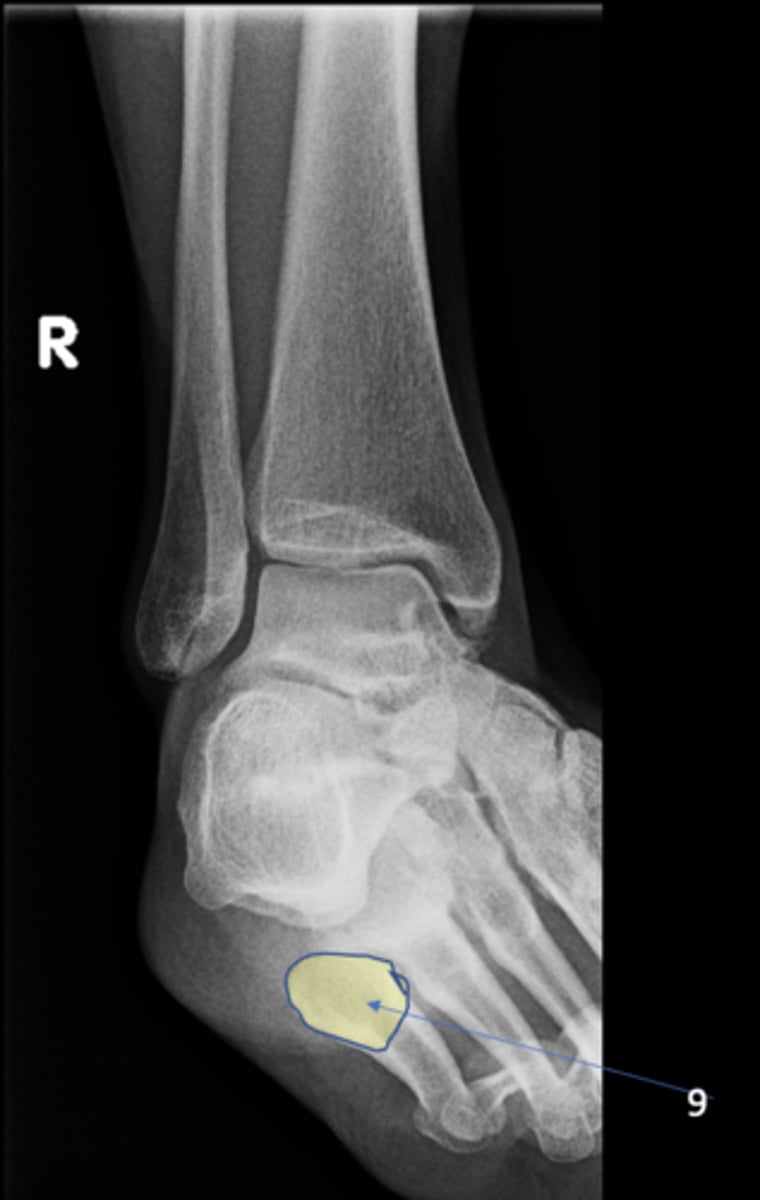

<p>ID 12</p>

13

New cards

Left anterior inferior iliac spine

ID 13

<p>ID 13</p>

14